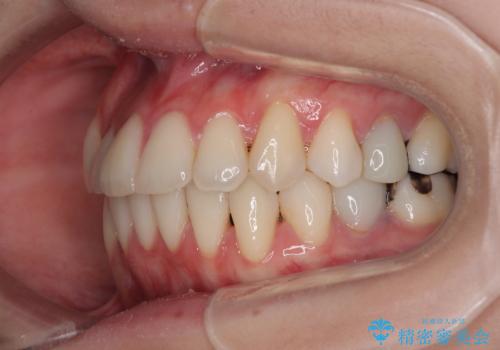

- 上下前歯のデコボコとクロスバイトを気にして来院された患者様です。

治療済みの処置歯が多いため、インビザラインを用いて矯正治療を行うこととしました。

下顎臼歯部にブリッジが装着されており、移動不可のため、IPR(歯と歯の間を削る)と歯列全体を拡大させることで、歯並びを整えていくこととしました。

インビザライン特有の奥歯の噛みにくさが治療後半に発現しましたが、無事に終了させることができました。